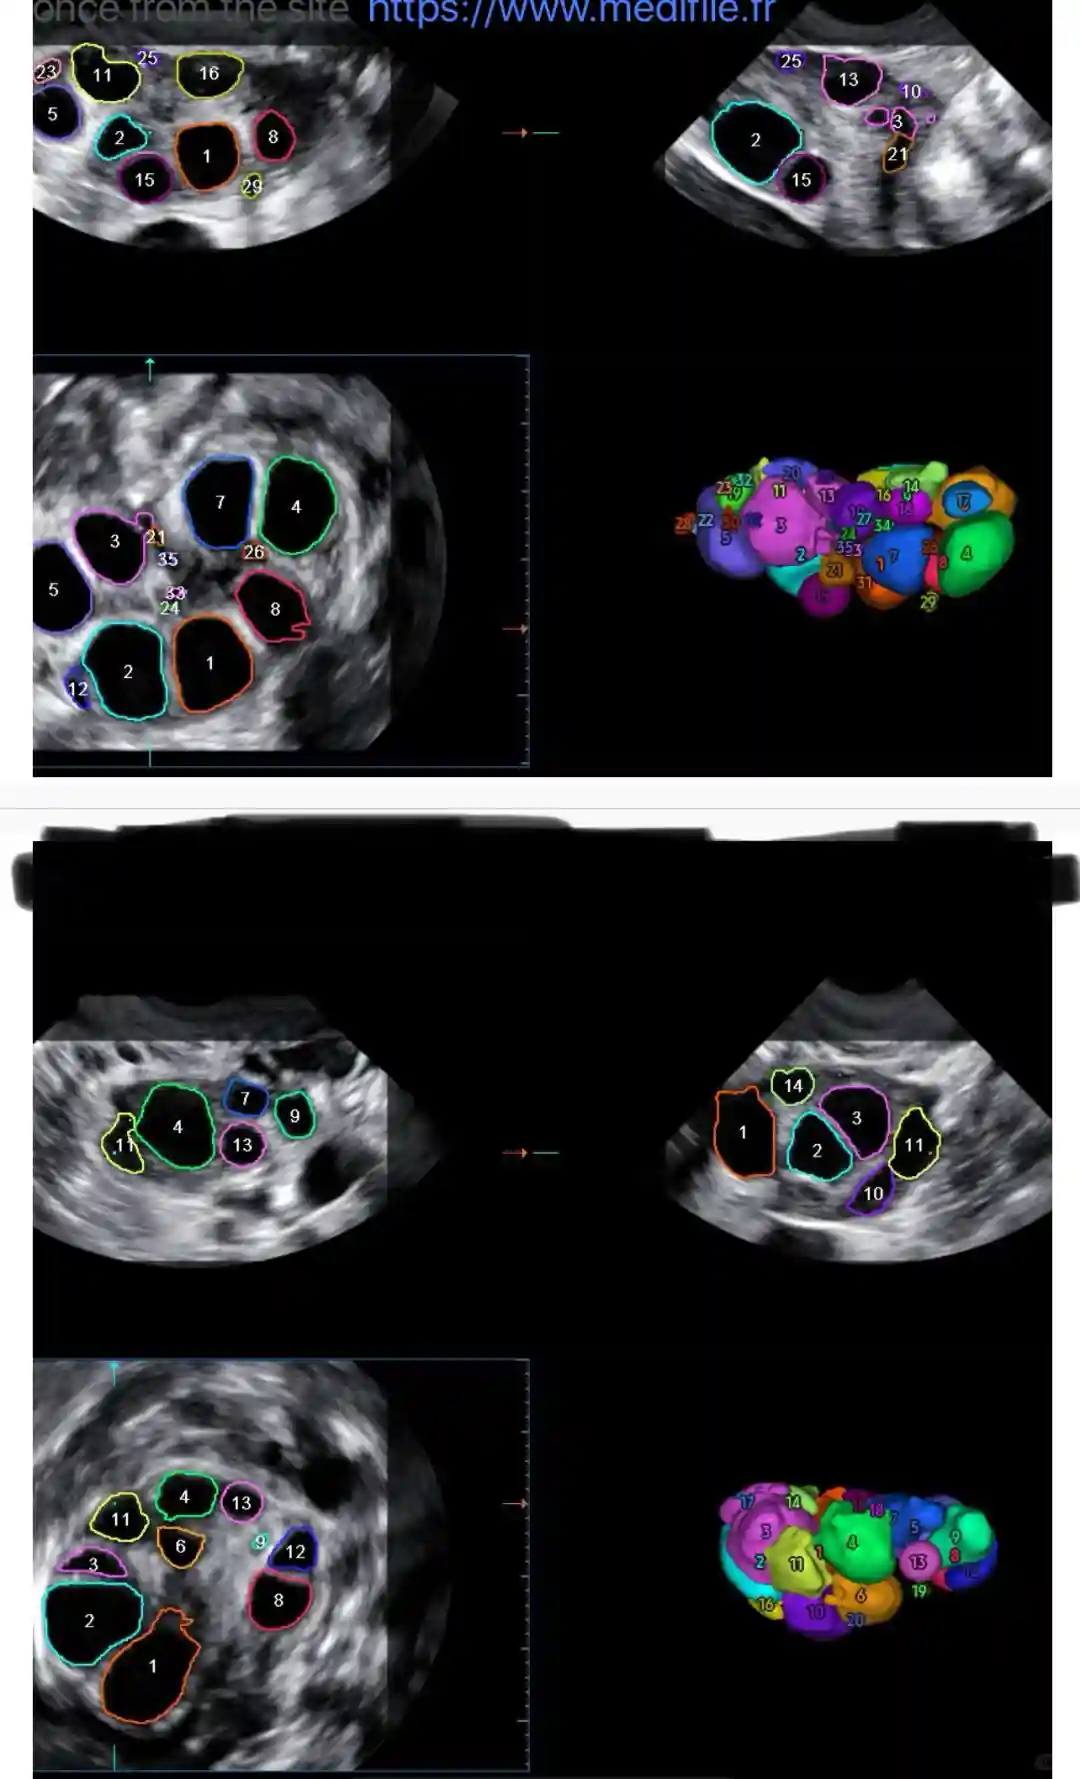

图567,打了6天Gonal-F和3天Fyremadel验血及B超结果